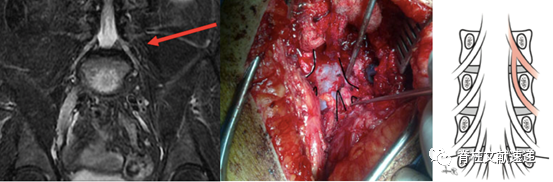

2.MR神经成像(MR neurography imaging)能够更清楚的显示异常神经根。

上图MR神经成像(右下)显示了双侧L5和S1并根异常。属于Neidre分型I型,最常见类型。

上图MR神经成像显示了左侧L5和S1并根异常。属于Kadish分型IV型或者Neidre分型II型,在L5/S1左侧椎间孔内有2根神经根穿出。

MR神经成像与术中对照。异常神经根为Neidre分型IA型,从上位神经根发出,然后与硬膜平行向下走形,从下一个椎弓根下穿出。

文献报道通过仔细阅MRI,神经根变异术前发现率约为40%。这就需要临床医生在阅片时格外认真,必要时行MR神经成像。但是,还有60%是术前不易发现的,这就需要每一台手术都要充满敬畏,不可大意。良好的无血术野、充分的照明和放大、谨慎的使用尖刀和钳子,能够降低神经根损伤的发生。